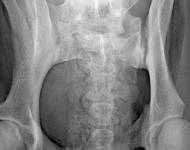

MVDr. Meloun: Lumbosakrální přechodový obratel